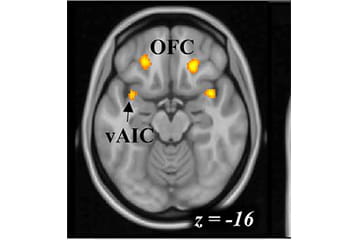

image of a brain scan

fMRI Study of Tasting Alcohol and Working

This study takes three and a half hours to complete. Participants undergo an MRI while going through the following sequence twice: tasting a drink (either alcoholic or non-alcoholic), working on a task, and then resting. The study and prerequisite in-person screening take place in Indianapolis at Goodman Hall and are conducted Monday through Friday. Participants in this study receive up to $150.